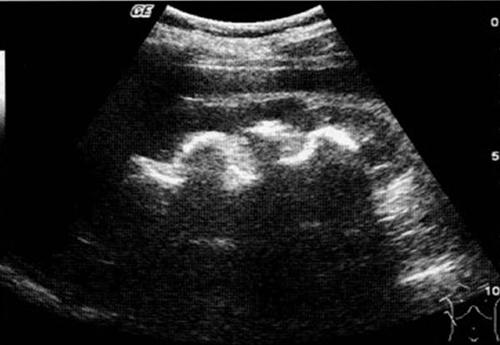

鹿角形肾结石属于肾结石中较复杂且常见的一种,特别是经济不发达的地方,其如鹿角生长,后期可逐渐填满肾脏的集合系统,占据整个肾盂及肾盏,因而治疗时取石困难。

摘要:鹿角形肾结石常见于肾盂分支进入肾盏处,通常存在于整个肾盂或至少一个肾盏的一种肾结石类型,此类结石具有复发率较高和清除较难的特点,临床上对该类患者若常规采取传统手术治疗,难以完全清除结石。目前作为泌尿外科的一个治疗重点。